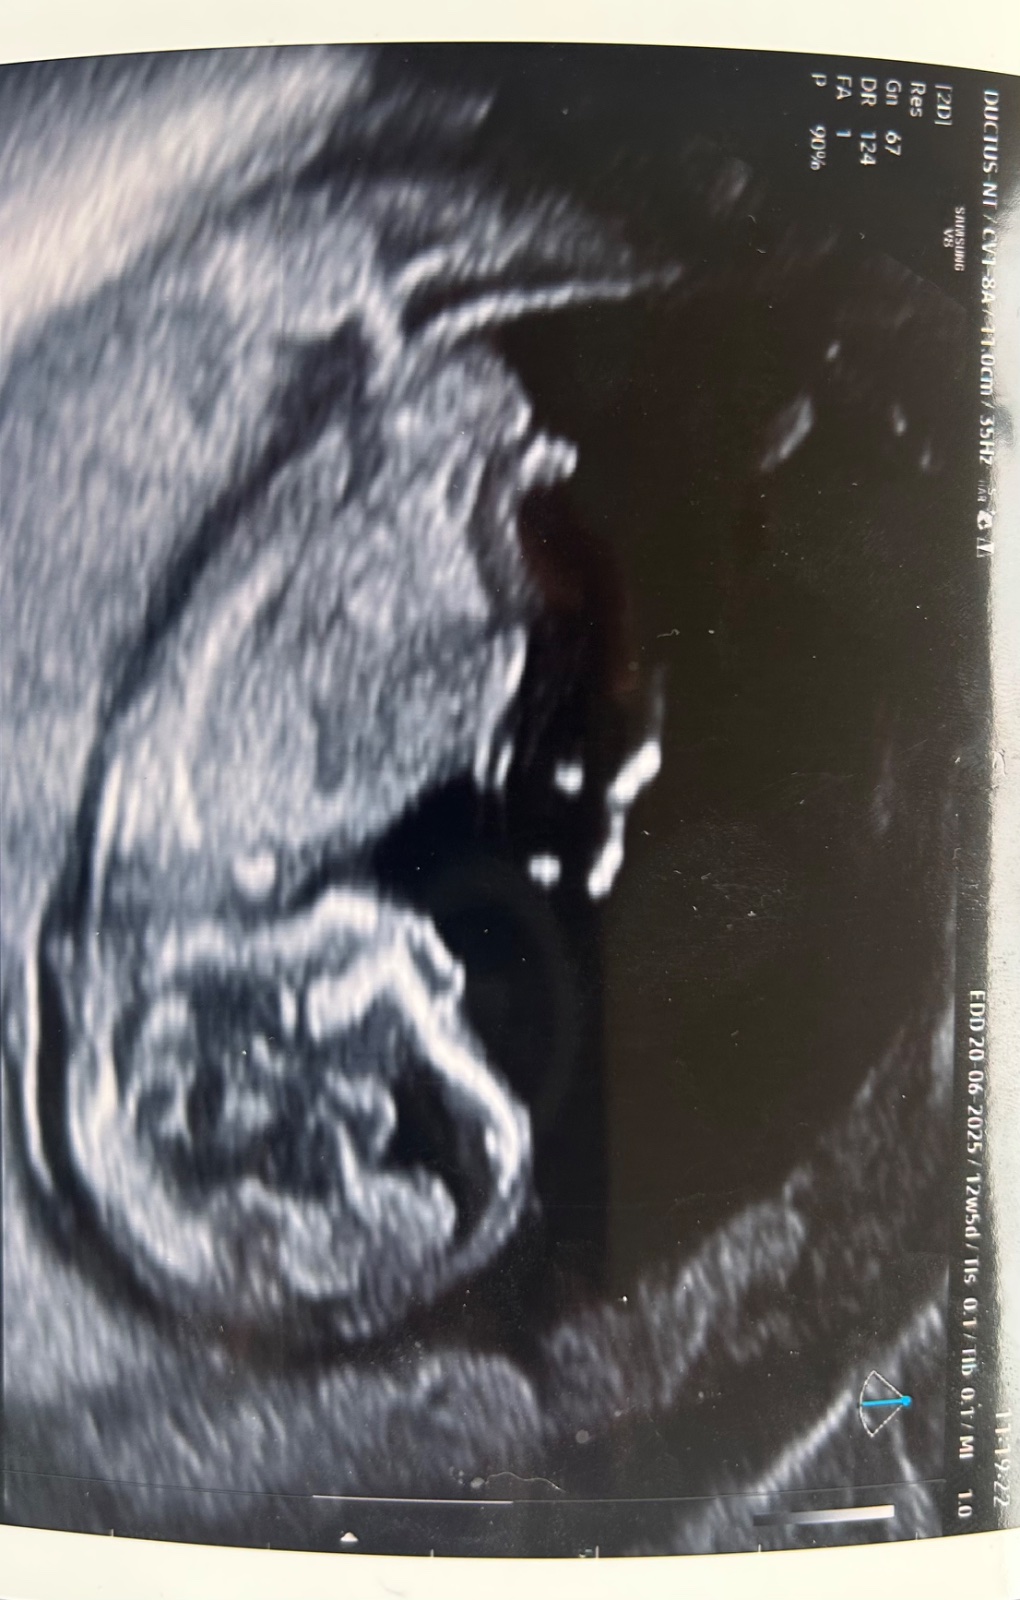

Určitě tě nemine 3D ultrazvuk.

Nebo také screening v 1. trimestru.

Důležité je, co říkal lékař. Poku nic, je brzy a poví ti to příště.